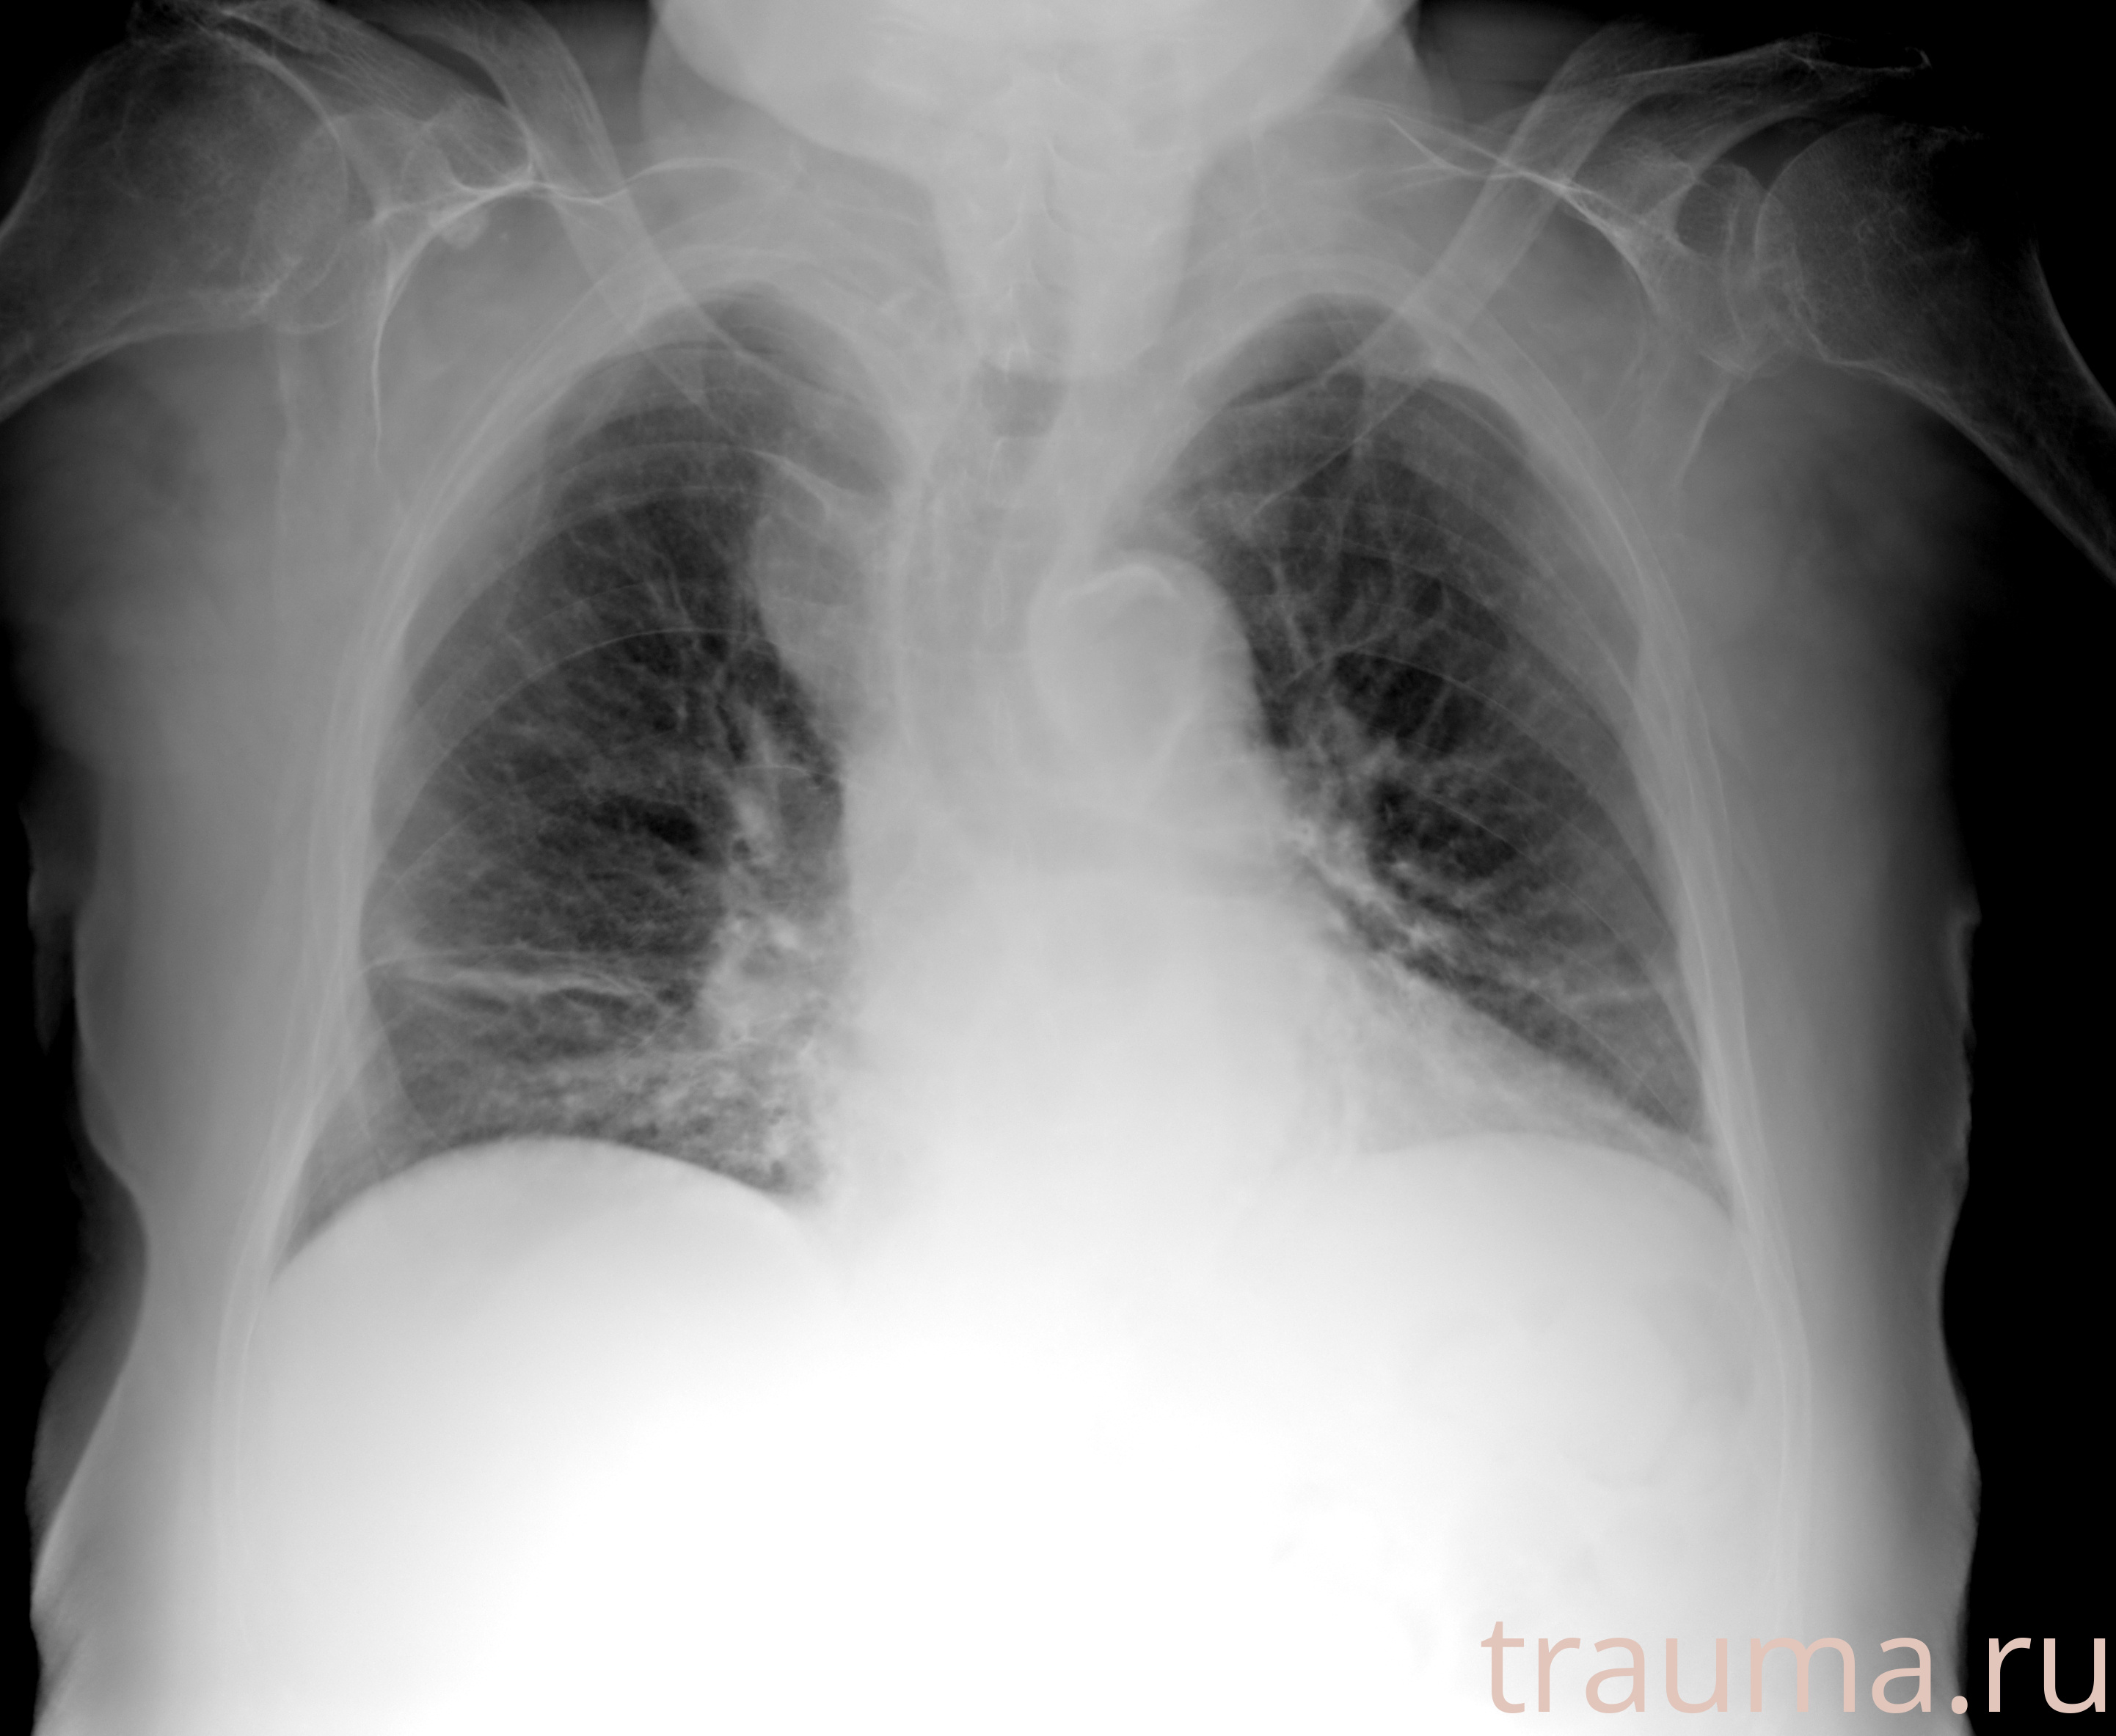

Перелом 3-5 ребер слева